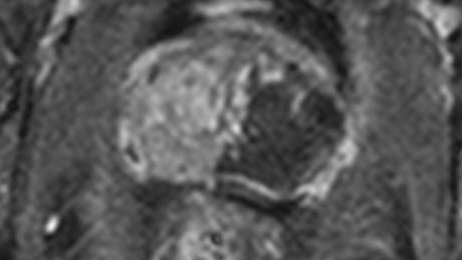

In 2018, @UCL research made significant advances in the diagnosis of prostate #cancer. Centre for Medical Imaging Prof Shonit Punwani (Shonit Punwani) discusses using MRI to better understand some of the most aggressive cancers. Read more here: bit.ly/2SGUK4r